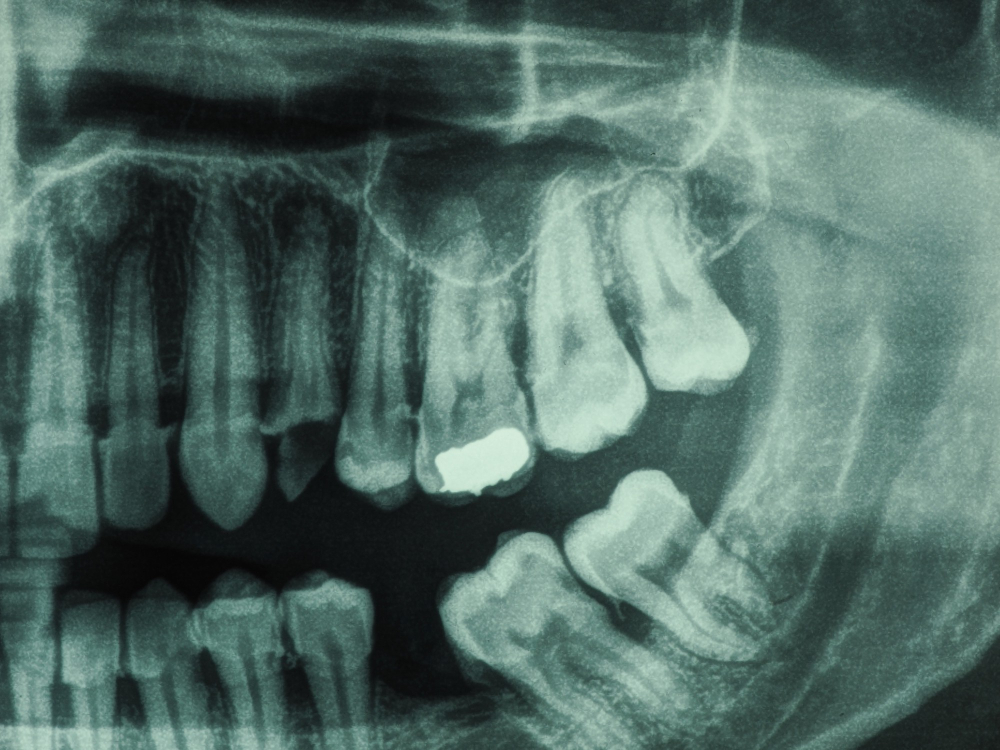

For a thorough understanding of your dental health, Sai Dental Clinic in Diva Thane offers dental X-rays as part of our comprehensive diagnostic services. Dental X-rays allow our team to see beyond the surface of your teeth and gums, identifying issues like cavities, bone loss, and infections that may not be visible during a regular exam. This ensures that we can provide precise and accurate treatment based on a complete understanding of your oral health.

Our clinic uses state-of-the-art digital x-ray technology, which reduces radiation exposure and delivers clearer images in less time. Whether you're coming in for a routine check-up or need a more in-depth analysis of a dental issue, x-rays are an essential tool for proper diagnosis and treatment planning.